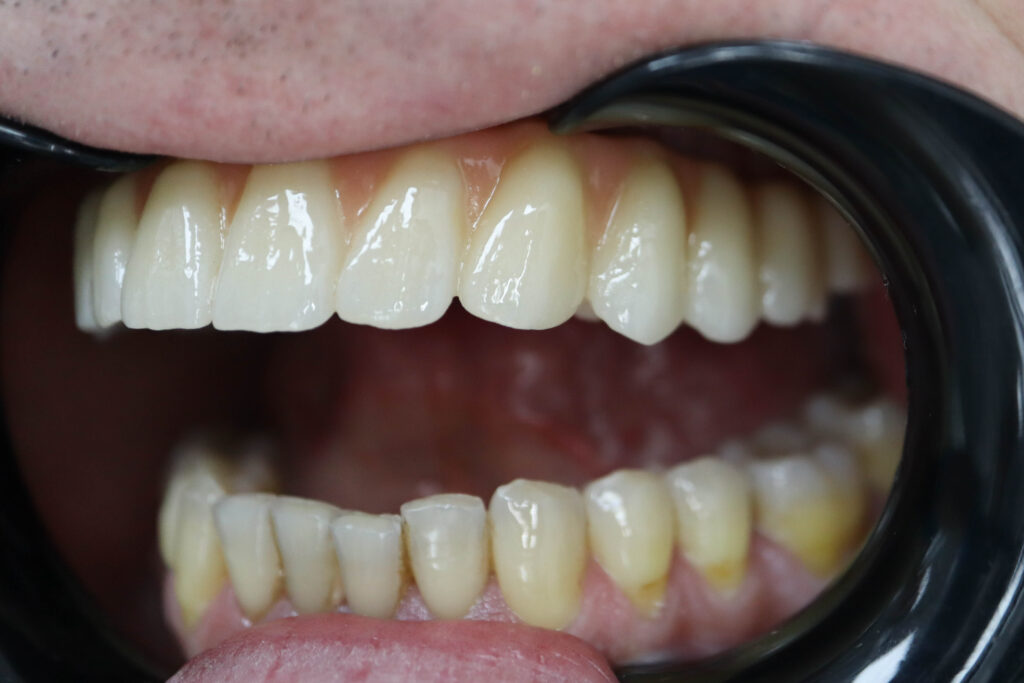

Результаты

результат имплантации SimplaDent

Спустя 25 дней был зафиксирован протез с опопрой на дентальные имплантаты из диоксида циркония с армированием из титана.